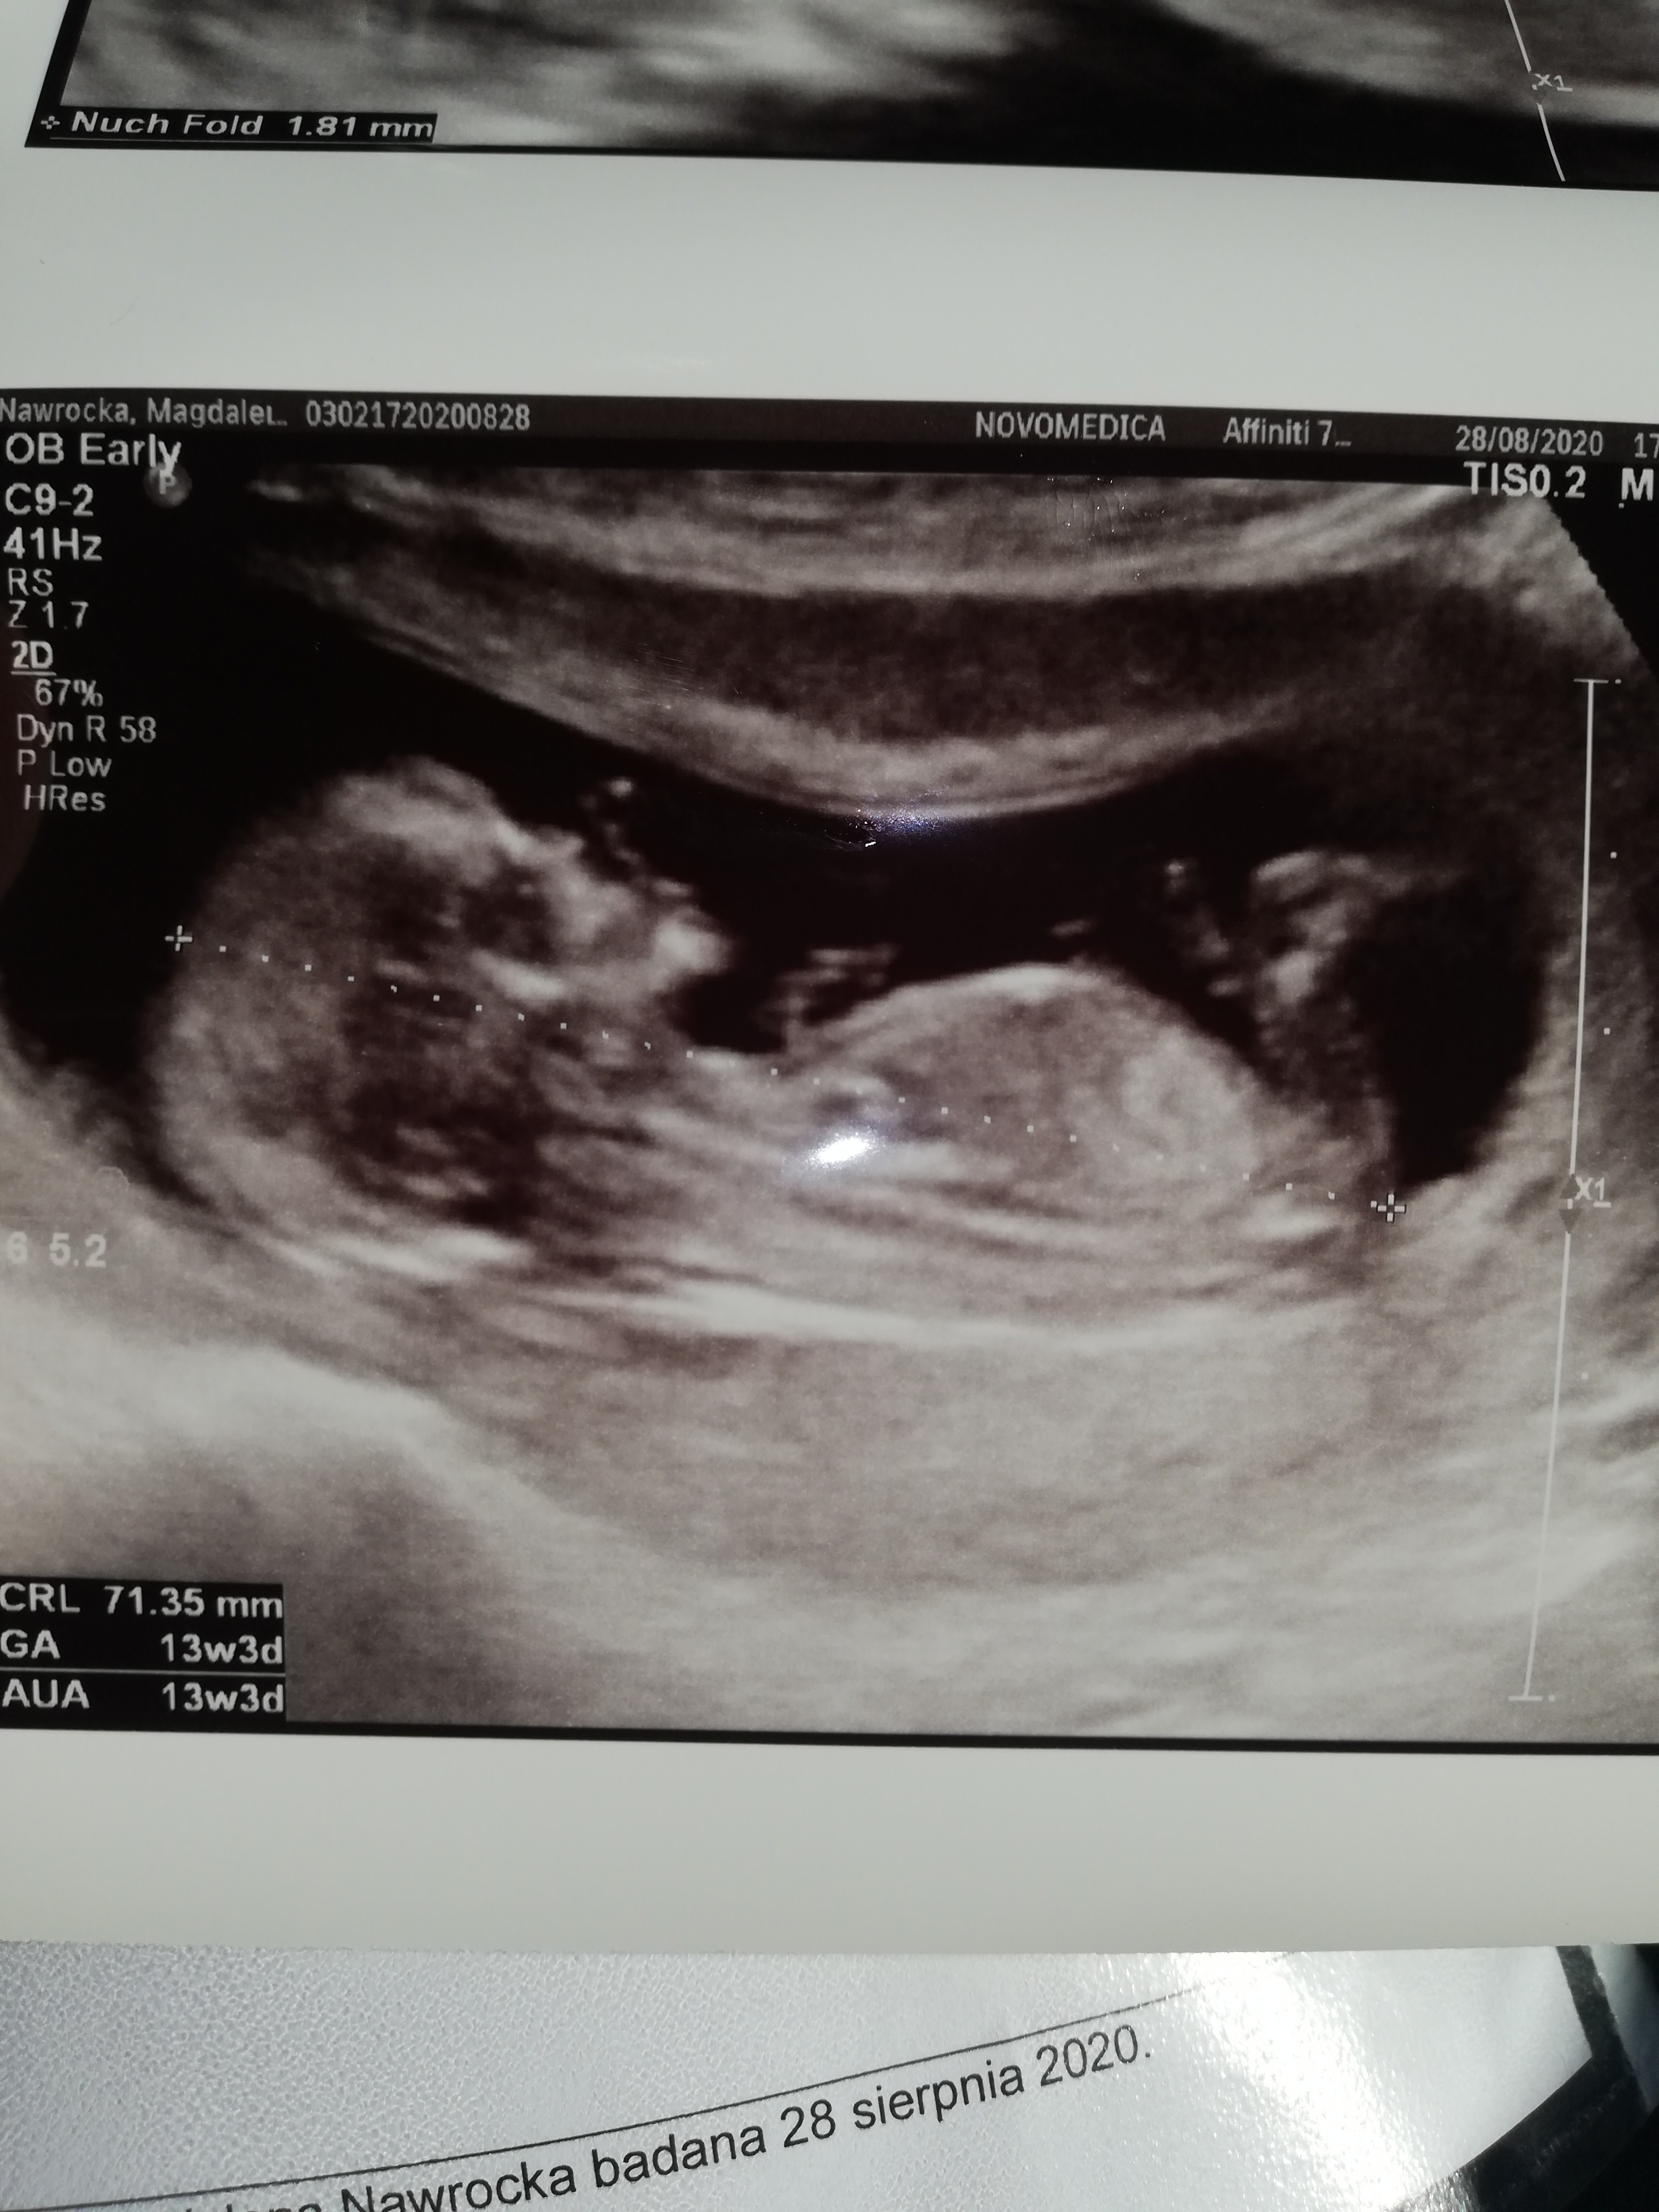

A to przezierność miałaś robiona jako prenatalne czy po prostu na USG? Właśnie nie wiem czy się dobrze zrozumiałam z lekarzem bo powiedziałam że chciałabym zrobić prenatalne USG i powiedział że zrobimy. I nie wiem czy po prostu zrobi mi zwykle badanie czy sprawdzi wszystko tak jak na prenatalnych kark, nos, itpWszystko dobrze, dzidzia ma prawie 5cm. Termin porodu wg usg i wg miesiączki taki sam. Dzidzia ssała kciuk. Jeszcze nie wiem czy dziewczynka czy chłopiec. Czekam na prenatalne 7.09. ale przezierność karkowa w normie.

USG 12 tydzień 4 dzień tak jak z okresu

zrobiłam tez test pappa przy następnej wizycie będzie wynik